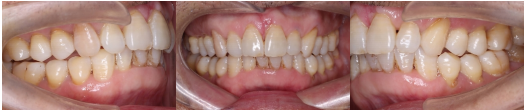

术前分析:咬合照片